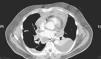

Paciente varón de 56 años, diagnosticado de una pancreatitis necrótica en su hospital de área. Tras una mala evolución, y con la sospecha diagnóstica de mediastinitis en la tomografía computarizada (TC), el paciente es trasladado a nuestro hospital. Inicialmente, al no presentar colecciones mediastínicas, se decide tratamiento conservador con antibioterapia empírica. Dos días después la TC de control muestra un aumento de la grasa mediastínica, colecciones mediastínicas con contenido aéreo, derrame pericárdico y pleural bilateral (figs. 1). Ante los hallazgos clínicos y radiológicos, se decide intervenir quirúrgicamente. Se practica una esternotomía media con extirpación de la grasa mediastínica necrosada, desbridamiento y drenaje de las colecciones mediastínicas existentes y drenaje pleural bilateral y pericárdico. El cultivo del material drenado es positivo para Candida parapsilosis y Pseudomona aeruginosa.

En un paciente con pancreatitis en el que aparece disnea, dolor torácico, fiebre, cianosis, taquicardia, fallo cardiaco agudo o un síndrome de la vena cava superior, hay que sospechar una complicación intratorácica. En nuestro caso, la pancreatitis se agrava con una insuficiencia respiratoria que requiere su ingreso en la unidad de cuidados intensivos y al realizar la TC se objetiva la afectación mediastínica y pleural.